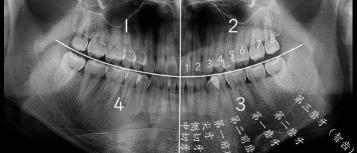

智齿是从正中的门牙往里数第八颗牙齿,也就是第三颗磨牙。它是发育、萌出最晚的牙齿,通常在4~5岁时形成牙胚,随后逐渐发育形成牙齿,一般17~25岁左右萌出,此时人的生理、心理发育都接近成熟,因此俗称“智齿”。

智齿的形态也是各种各样,基本罗列如下几种,实际会有更多复杂情况。